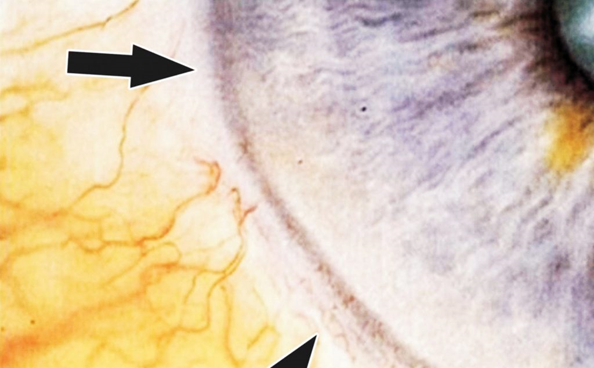

Arcus Lipóides

Este sinal que corresponde ao Anel de Sodio ou Colesterol da Escola Jensen ou da Íris Colesterolêmica da Escola de Deck. Como já se sabe trata-se de uma alteração do metabolismo dos lipídeos e de sais minerais inorgânicos. cujos metabólitos acabam por depositar na córnea. Assim como o Arcus Lipóides com Barras Marrons um sinal de alterações de ordem hepática ou mesmo. intoxicações intestinais. associadas a um dismetabolismo das gorduras e de metais “inorgânicos”.

Convém nesta eventualidade verificar na iris se realmente o figado e os intestinos apresentam alguma marca topográfica. que pode funcionar como dado corroborativo, ou mesmo indicar início de doenças.